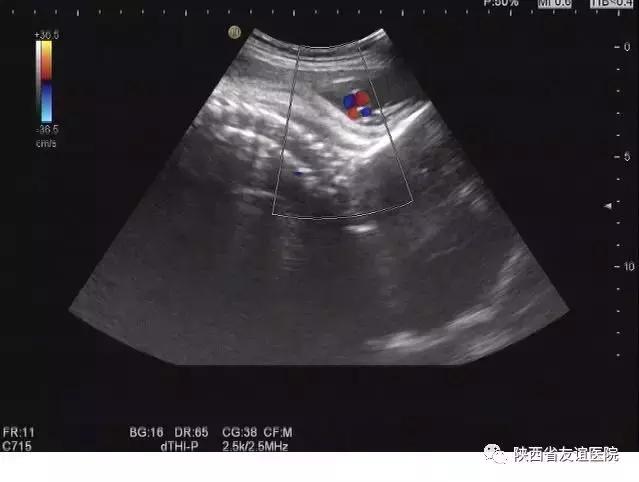

宫外孕B超图

其实,这些想法都是不对的。孕早期是排除宫外孕和胚胎是否正常发育的关键时期,早期的检查可以明显地降低事故的发生率。在平时的检查中,经常会看到这样一些孕妇,来产检时是以孕12周伴阴道出血来就诊的,但是B超显示的发育程度与孕周明显不符,甚至出现了胚胎停育的现象;还有一些人甚至有严重的腹痛及阴道出血,并伴有休克,甚至危及生命,经B超检查诊断为宫外孕破裂,。而这些人中,很多是第一次进行B超检查的。